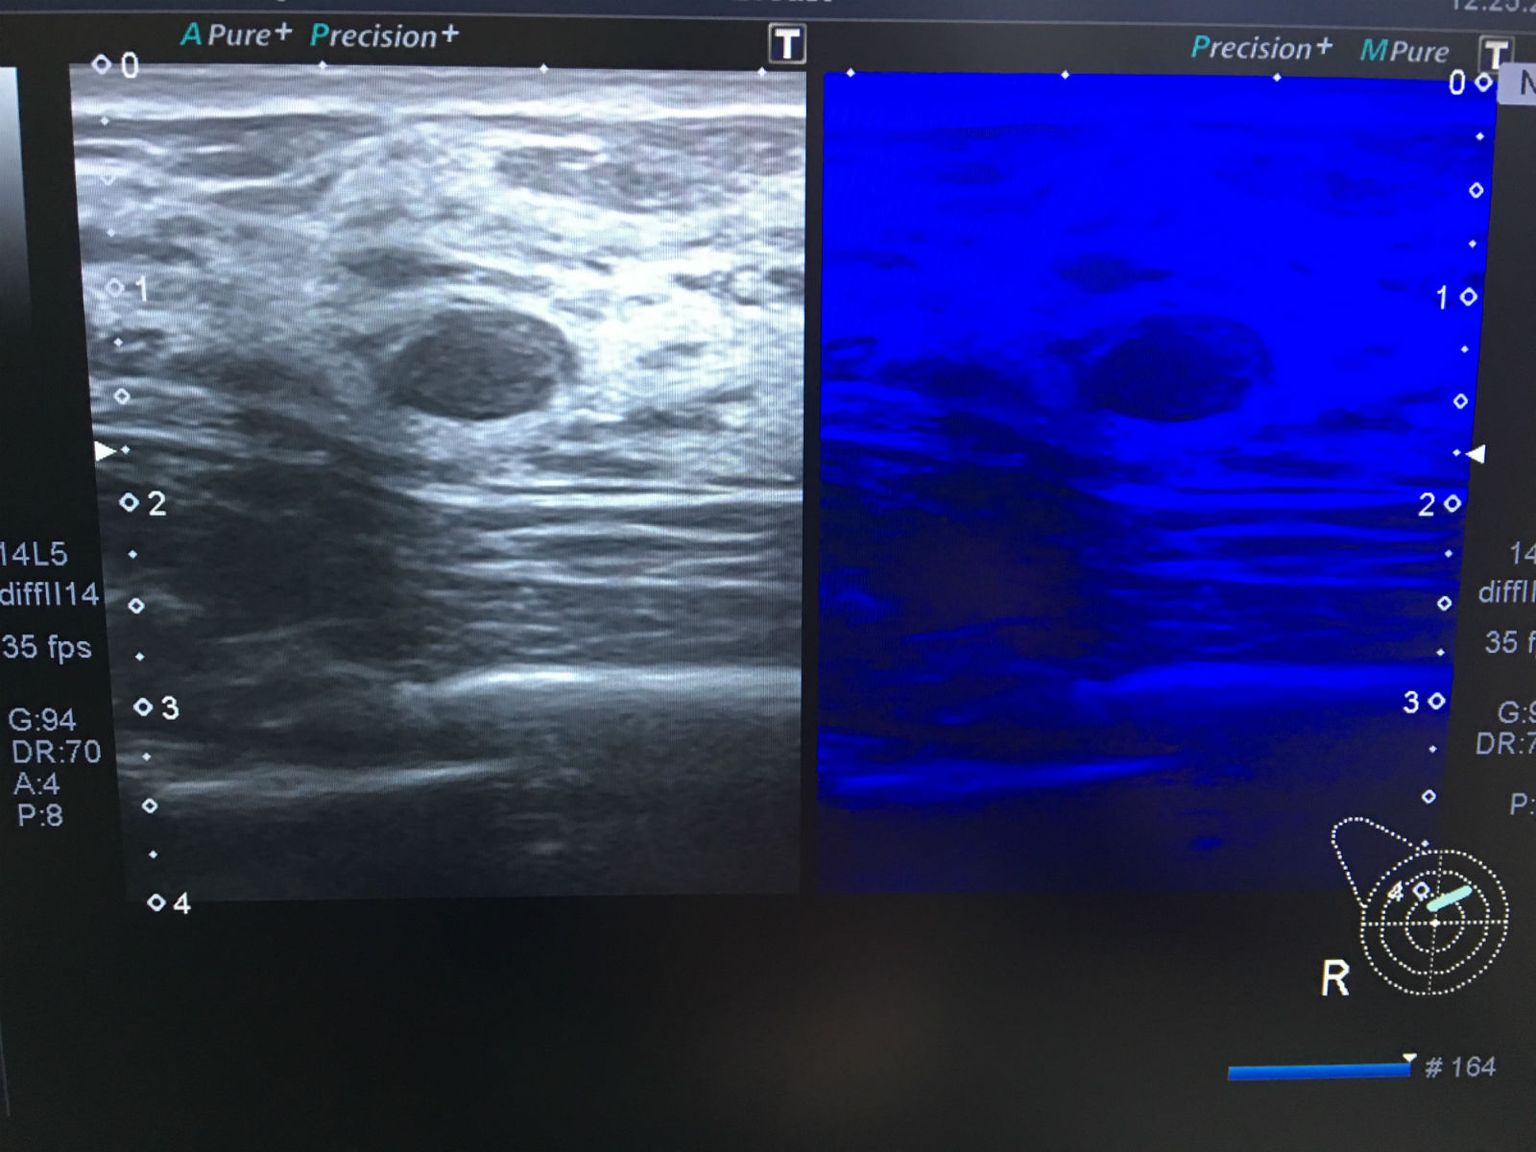

• Micropure za uočavanje mikrokalcifikata Foto: ultrazvuk-tarle.hr